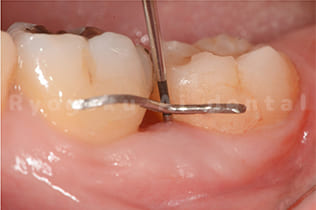

- 歯周ポケットの確認

プローブで歯周ポケットの状態を確認します。

- 歯の動きが大きい場合は下記の写真のようにワイヤーで固定する場合があります。